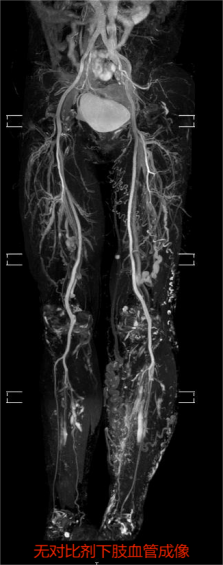

为了进一步提高检查效率,科室还升级了相对分设备检查。放射科主任邱迎伟表示,相对分设备检查是根据设备优势和检查部位进行分类,也就是不同部位的检查用不同设备来做,物尽其用。比如神经、血管优势品牌设备,对于全身大范围血管显像更全面,外周神经显示清晰;还可以在无对比剂下成像,不打药更安全。